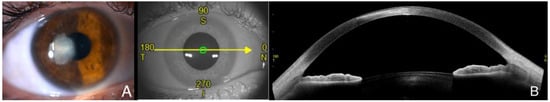

Clinical examination of the eye (A) and AS-OCT correlation (B) months after the episode. Antimicrobial treatment was tapered until complete resolution of the symptoms. At the end of the episode, the clinical examination demonstrated a paracentral leukoma, and AS-OCT displayed regular hyperreflectivity in that area in a thinned stroma with complete restoration of the epithelium. The clinical course was monitored with physical examination in slit lamp and imaging using AS-OCT scans. In those images, the main findings were increased corneal thickness, hyperreflective stromal lesions and appearance of cystic spaces. These findings have been described in fungal keratitis monitored by AS-OCT in previous reports [4] and can be a useful tool to consider stromal affectation. Although it is not a routine exam in most cases, when compared to other tests such as in vivo confocal microscopy, AS-OCT can be helpful to assess the severity of the corneal infection by measuring the extension and depth of the infiltrate and identifying other features, such as corneal haze and epithelial defect. Specifically, in infectious keratitis with corneal opacity, it can be used as a tool to diagnose endothelial plaques and register the response to antimicrobial treatment [5]. It can also be useful to perform a differential diagnosis from other microbial causes with characteristic features in AS-OCT—for instance, Acanthamoeba spp. keratitis. Once the infectious episode has ended, corneal scarring can be evaluated with AS-OCT by performing a corneal densitometry and topography. The arrow is correspondence of the en face picture with the selected section on the AS-OCT, the letters are N nasal, S superior, T temporal and I inferior, and the numbers are the gradation of the 360 degrees of the cornea.